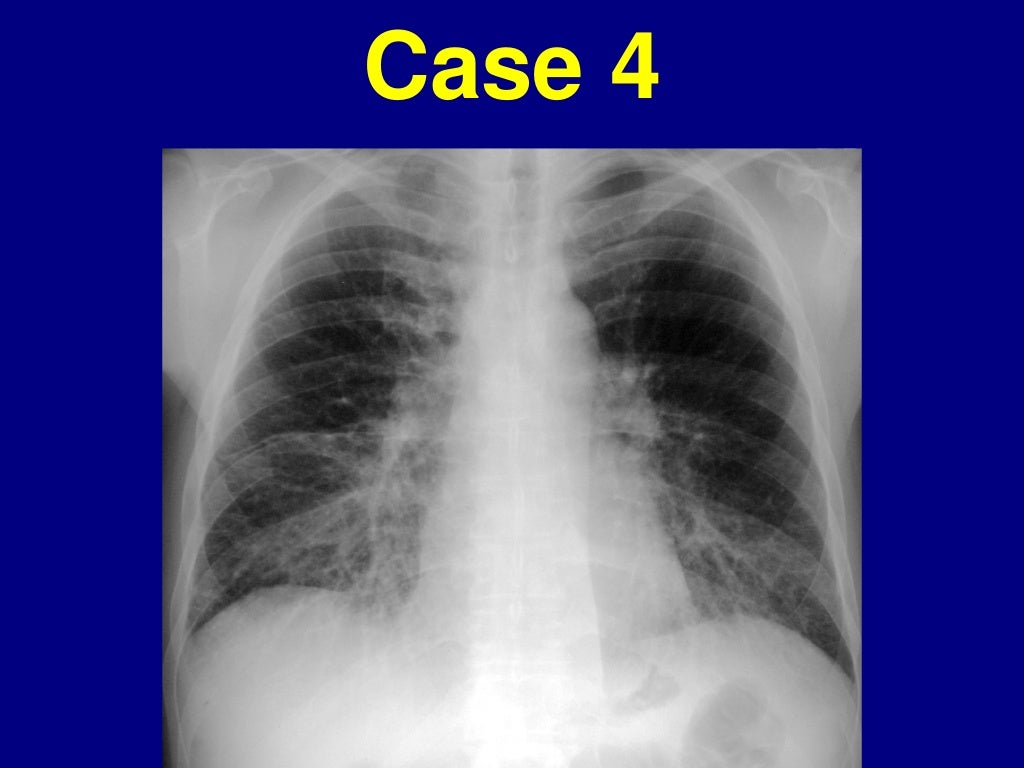

Radiographics Ild . Interstitial lung abnormalities (ilas) represent radiologic abnormalities incidentally detected on chest computed tomography (ct). Idiopathic pulmonary fibrosis, which is characterized by the morphologic pattern of. Contemporary approaches to interstitial lung disease classification. Approximately 30% of patients with ild report cough. Interstitial lung abnormalities (ilas) are common incidental findings at ct, which progress over 5 years in more than 50% of. Accurate diagnosis of ild is essential for guiding treatment and estimating prognosis; Ild typically presents with dyspnea on exertion. In this review, we present an algorithmic approach for assessing ilds based on identifying and understanding key imaging features to aid in narrowing a differential diagnosis or reaching a specific diagnosis.

Interstitial lung abnormalities (ilas) represent radiologic abnormalities incidentally detected on chest computed tomography (ct). Idiopathic pulmonary fibrosis, which is characterized by the morphologic pattern of. Accurate diagnosis of ild is essential for guiding treatment and estimating prognosis; Ild typically presents with dyspnea on exertion. Contemporary approaches to interstitial lung disease classification. In this review, we present an algorithmic approach for assessing ilds based on identifying and understanding key imaging features to aid in narrowing a differential diagnosis or reaching a specific diagnosis. Approximately 30% of patients with ild report cough. Interstitial lung abnormalities (ilas) are common incidental findings at ct, which progress over 5 years in more than 50% of.